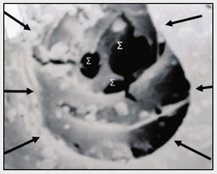

Έρευνες έχουν αποδείξει ότι με την αύξηση της έκτασης ή/και του βάθους της κοιλότητας εντός της οδοντίνης αυξάνεται ταυτόχρονα και η διαπερατότητά της. Το φαινόμενο αυτό εξηγείται από το γεγονός ότι ο αριθμός και η διάμετρος των οδοντινοσωληναρίων αυξάνονται με την αύξηση του βάθους της ίδιας κοιλότητας (Εικ. 6). Έτσι στο όριο οδοντίνης αδαμαντίνης ο αριθμός των οδοντινοσωληρίων κυμαίνεται από 10.000 έως 20.000/mm² και η διάμετρός τους από 0.5 έως 1.2 μm. Ο αριθμός αυτός στο όριο οδοντίνης πολφού πολλαπλασιάζεται και φθάνει να κυμαίνεται από 30.000 έως 60.000/mm², ενώ η διάμετρός τους από 1.2 έως 3 μm. Επομένως, στην κλινική πράξη, η αναμενόμενη βλάβη του πολφικού ιστού θα είναι μεγαλύτερη σε κοιλότητες με βαθιά τερηδόνα, επειδή οι τοξίνες των μικροβίων έχουν τη δυνατότητα ευκολότερης πρόσβασης προς αυτόν, ειδικά στα σημεία των πολφικών κεράτων όπου παρατηρείται μεγαλύτερη διαπερατότητα της οδοντίνης.Εικ. 6: Στόμια οδοντινοσωληναρίων στο Ηλεκτρονικό Μικροσκόπιο Σάρωσης (x 10.000). Μέσω ενός επιφανειακού στομίου (βέλη) παρατηρείται, στο βάΘος της οδοντίνης, η παρουσία τριών άλλων στομίων (Σ).

Έρευνες έχουν αποδείξει ότι με την αύξηση της έκτασης ή/και του βάθους της κοιλότητας εντός της οδοντίνης αυξάνεται ταυτόχρονα και η διαπερατότητά της. Το φαινόμενο αυτό εξηγείται από το γεγονός ότι ο αριθμός και η διάμετρος των οδοντινοσωληναρίων αυξάνονται με την αύξηση του βάθους της ίδιας κοιλότητας (Εικ. 6). Έτσι στο όριο οδοντίνης αδαμαντίνης ο αριθμός των οδοντινοσωληρίων κυμαίνεται από 10.000 έως 20.000/mm² και η διάμετρός τους από 0.5 έως 1.2 μm. Ο αριθμός αυτός στο όριο οδοντίνης πολφού πολλαπλασιάζεται και φθάνει να κυμαίνεται από 30.000 έως 60.000/mm², ενώ η διάμετρός τους από 1.2 έως 3 μm. Επομένως, στην κλινική πράξη, η αναμενόμενη βλάβη του πολφικού ιστού θα είναι μεγαλύτερη σε κοιλότητες με βαθιά τερηδόνα, επειδή οι τοξίνες των μικροβίων έχουν τη δυνατότητα ευκολότερης πρόσβασης προς αυτόν, ειδικά στα σημεία των πολφικών κεράτων όπου παρατηρείται μεγαλύτερη διαπερατότητα της οδοντίνης.